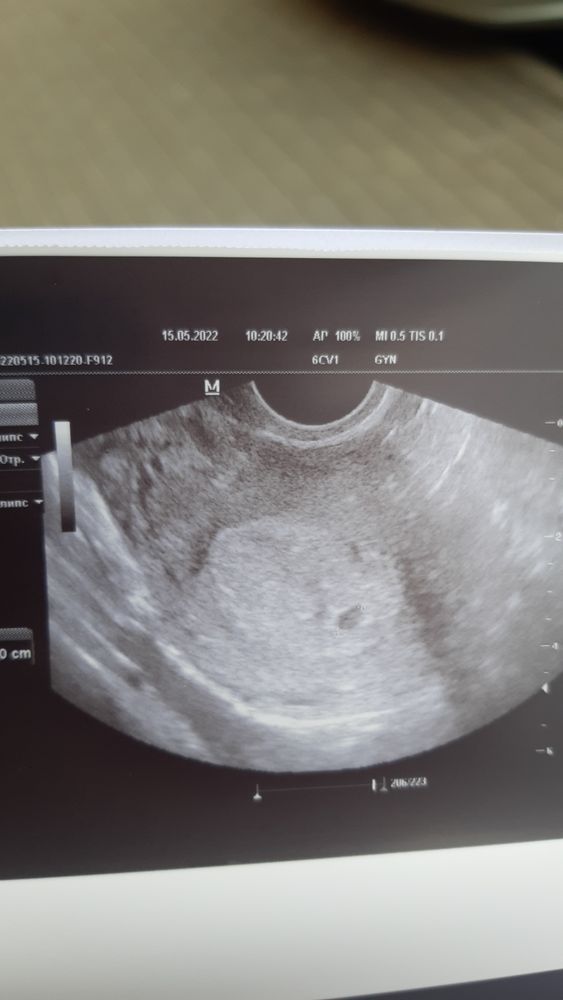

УЗИ на 20 дпо

Беременность- 1 триместр ( только до 10 недель)Только что с узи.

Девочки скажите пожалуйста, нормально ли что желточный мешочек не визиализируется ?

Поздравляю🌷🌷🌷! Легкой беременности и родов в срок! У меня с дочкой на таком сроке 5.0 нед. свд тоже было 6 мм и жм и эмбрион не визуализировался. Через 10-14 дней сходите еще на узи уже должно все появиться и сердцебиение тоже. Не переживайте 😊